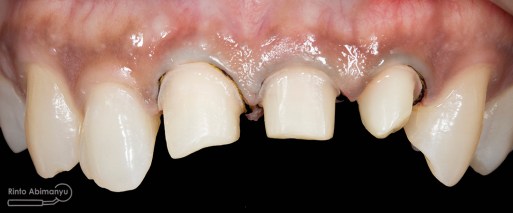

ini hasil preparasi gigi-giginya…